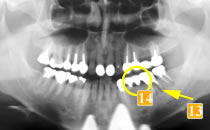

61歳男性

初診時、歯の根の先にかなり大きな膿の袋ができてしまっています(

)。

根が割れている、ひびが入っているという可能性も大いにありました。

-

は本来なら抜歯するケースですが、何とか残せないかと一度抜いて根の治療をし、再度植えました(

)。“再植術”といいます。

は最初の状態と同じ様にブリッジにすると負担が大きく、すぐダメになってしまう可能性が高いと判断し、同様に、この歯を何とか残すために歯のない部分はインプラントという治療法を選択しました。これならつながないでいいですし、インプラントでも噛む力が負担できるのでほかの歯を守れます。

歯がない部位(

)にはインプラントを植立しました。もし再度ブリッジにした場合

再植した歯への負担過重によって痛みが出れば、支えているもう一方の歯への負担も増します。

そうして負担が増加することで、右下奥歯は2本欠損することになったかもしれないのです。 しかし、この3本の歯をそれぞれ独立させることで、相互に保護しあう状態となり、結果、歯を残すことができました。